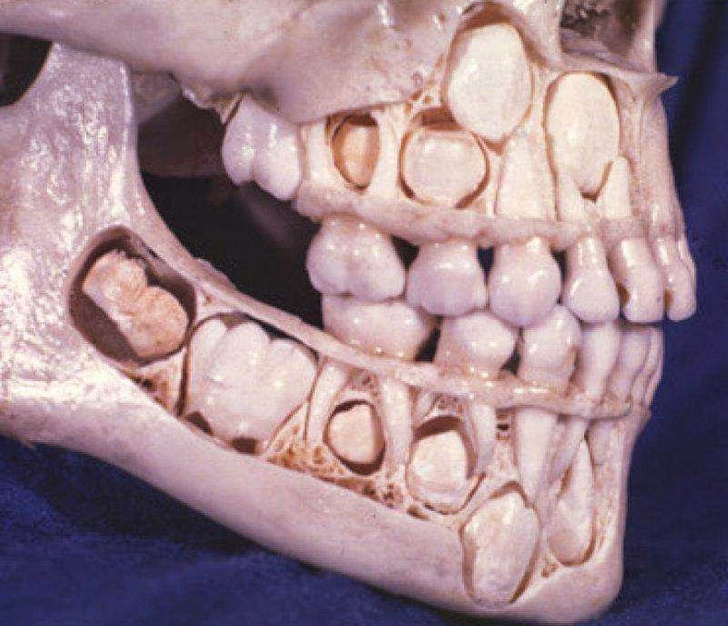

10. Đây là hình ảnh về những chiếc răng trước khi mọc.

![]() |

| Ảnh: BrightSide |